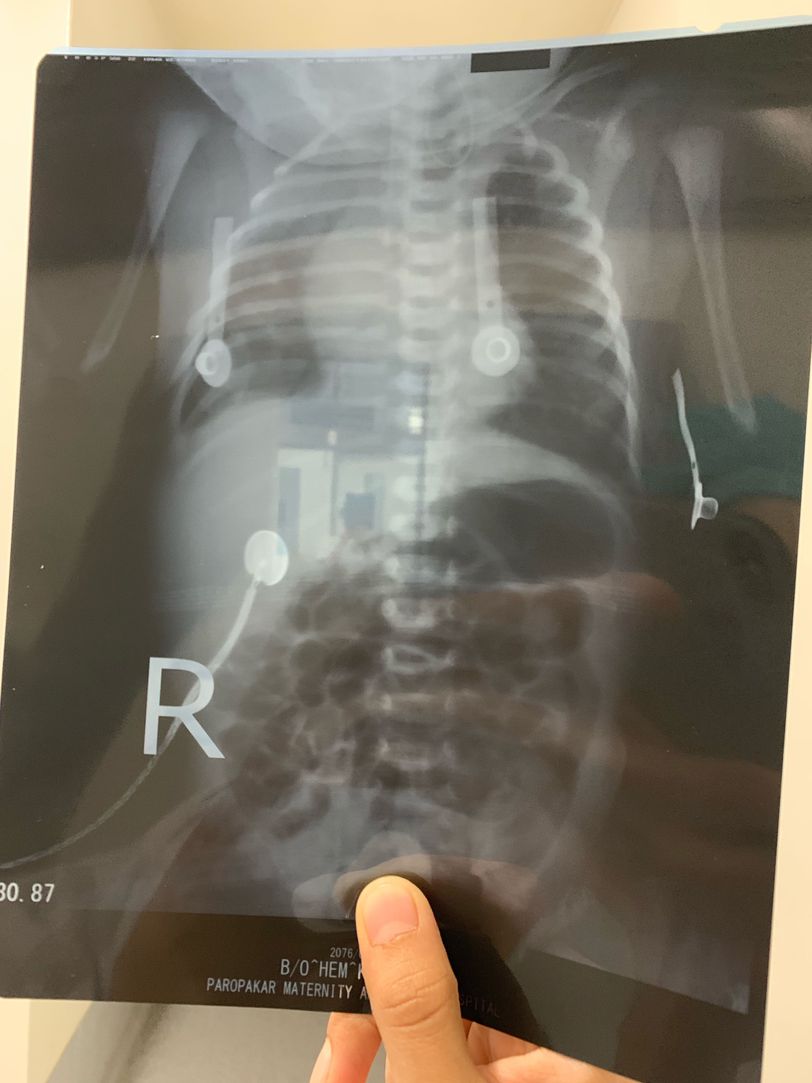

Tracheoesophagial Fistula

TOF

Xray

Neonate